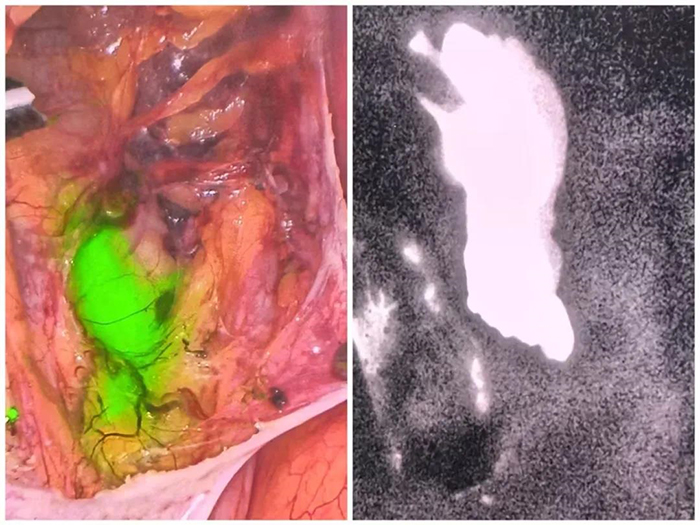

针对陈某的复杂病情,我院妇科一病房高天明主任医师团队充分结合其乳腺癌治疗史、内分泌治疗反应及子宫内膜癌诊断结果,量身定制了个性化手术方案。9月3日,在全身麻醉下,团队为陈某实施筋膜外全子宫切除术+双侧附件切除术+前哨淋巴结活检术。与传统系统淋巴结切除相比,此次手术创新性采用宫颈注射吲哚菁绿的方式,借助荧光腹腔镜清晰显影淋巴结及淋巴管,实现了双侧前哨淋巴结的精准切除,不仅大幅缩短手术时间,更有效降低了淋巴水肿、淋巴囊肿及感染等术后并发症风险。术后,陈某恢复顺利,现已顺利出院。

荧光腹腔镜下盆腔前哨淋巴结显影图